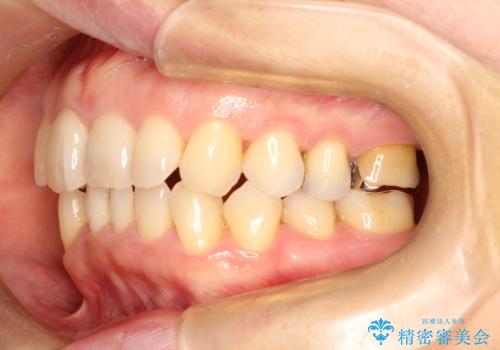

今回の治療では、右上5番の抜歯スペースを活用して八重歯(3番)を後方へ誘導しました。

インビザライン独自の3Dシミュレーションに基づき、必要な歯だけをピンポイントで動かすことで、抜歯を伴う大きな移動も効率的に行いました。

治療の結果、突出していた八重歯はきれいなアーチに収まり、左右対称でバランスの取れた口元になりました。インビザラインは自由に取り外しができるため、治療期間中も口腔内を清潔に保ちやすく、患者様もストレスなく治療を完了されました。